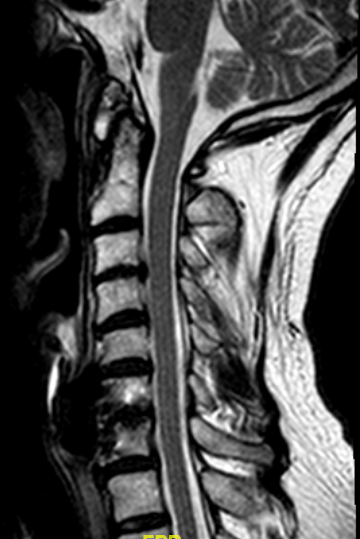

RM sagital T2.

La flecha azul marca el espacio que ocupa la prótesis, la flecha roja la estenosis foraminal